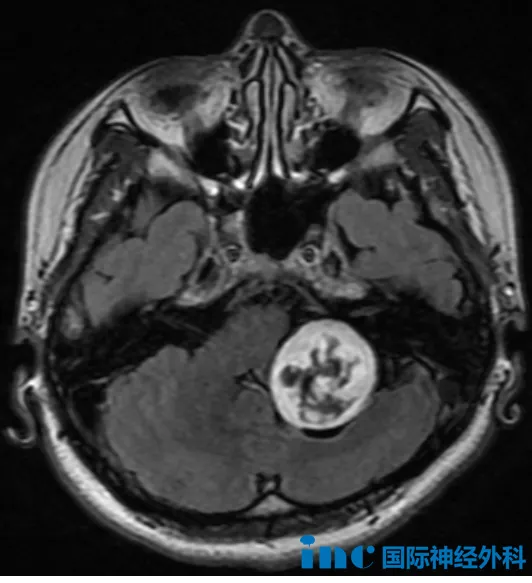

林女士(化名)的诊疗经历同样引人关注。一次意外摔倒后的检查发现左侧桥小脑角区存在约36×32mm的占位病变。鉴于手术高风险,患者接受了射波刀放疗治疗。

然而放疗后肿瘤未见明显缩小,却逐渐出现左侧面部肌肉抽搐、眼周跳动、耳鸣头晕等症状。更令人担忧的是,病变性质始终未能明确。

巴教授详细分析影像资料后指出:"这个增强病灶位于左侧小脑桥角区,累及颈静脉孔。从形态学判断,可能来源于后组颅神经的神经鞘瘤,但也不排除其他肿瘤类型。目前未见恶性征象,基本可判定为良性病变。"

教授强调:"手术切除是明确可行的治疗方案。我从事神经外科工作42年,完成过多例类似手术,效果均较理想。虽然既往放疗可能增加神经与肿瘤的粘连程度,但手术中会尽力保护神经完整性。当前应尽快手术,任何延误都可能导致肿瘤继续生长,增加后续治疗难度。"